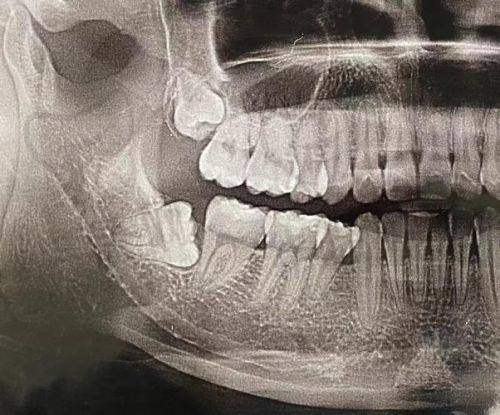

成都郫都嘉仁口腔门诊部是一家专科口腔医疗机构,其医护团队由经验多、口腔技术实力强的口腔医师和护理人员组成。在成人松动牙拔除方面,医生们具备扎实的专精知识和丰富的临床经验。他们会利用精良的设备,如数字化口腔摄影仪、口腔CT等,对患者的口腔情况进行全方面检查。通过这些检查,医生能够正确判断牙齿的松动原因、牙根情况等,从而制定出更适合患者的拔除方案,确保拔牙过程安心、有效。